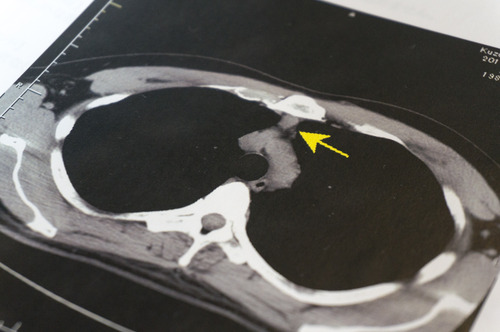

「そう!自覚症状がなくてもCT検査によって異常が見つかることは珍しくないのよ。こちらはカズマ@ひらつーの心臓の上ぐらいの体の断面の画像。CT検査によって、小さい腫瘍が見つかったわ!黄色い矢印のとこね。」

全員

「ひゃ〜こわい!」

初期のころは自覚症状がほとんどなく、大きくなっていくにつれて痛みや出血が伴っていきます。

(肺がんの場合、痰に血がまじるなどの症状がでることも。)

この腫瘍がもしがんだったら…場合によっては治療が遅れてしまうこともあるのです。